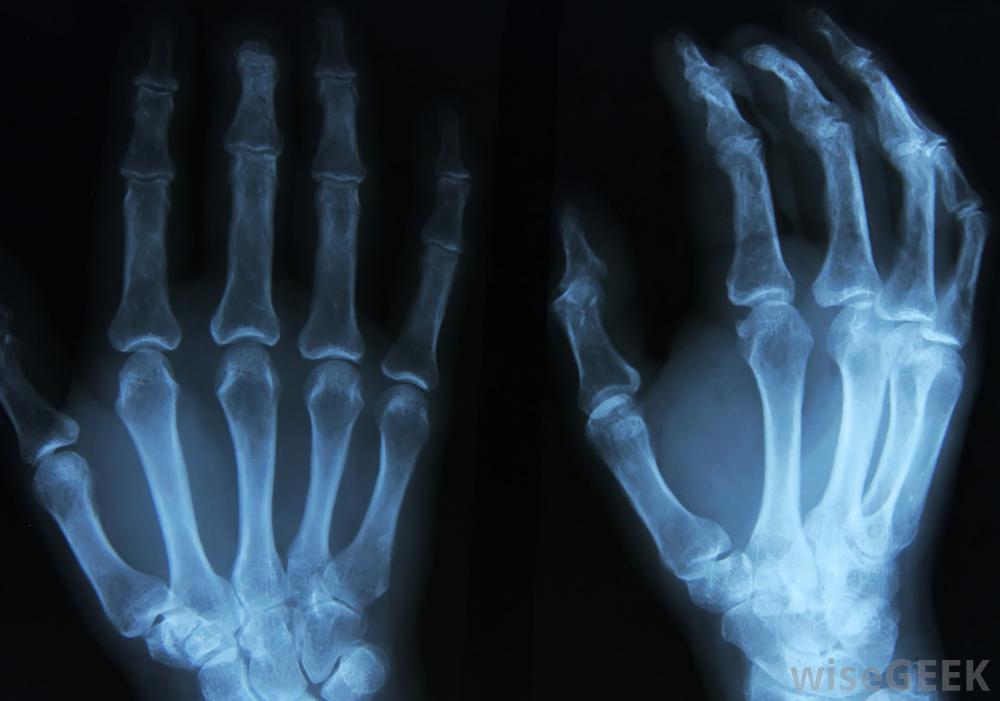

可以在X光片上发现神经节细胞瘤。这些肿瘤发生在自主神经细胞中。有时,它们开始产生激素,导致症状有腹泻、体重减轻、毛发过度生长等,因为身体适应了过量的荷尔蒙分泌。在其他情况下,它们会对周围的解剖结构造成压力,导致呼吸急促等症状。神经节细胞瘤可能在体检时可以摸到,或者可以在对身体的医学成像研究中看到,比如超声波或X光片。

切除神经节细胞瘤需要手术。有时,患者可以感觉到神经节细胞瘤,因为它靠近表面或在他们会注意到的地方,比如手的神经。会产生一个小的肿胀,质地稍有弹性,操纵肿胀可能会引起刺痛或疼痛感发现皮肤下有肿块的人应该寻求医学评估,以了解肿块的性质并接受治疗,如果需要,切除神经节细胞瘤的手术并发症可能包括麻醉不良反应。